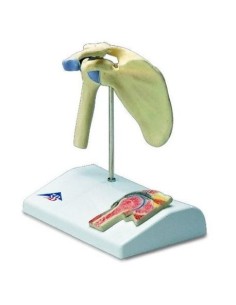

Mini jeu d'articulations avec évidence de la musculature 3B Scientific 1019518

Modèle anatomique fonctionnel de la coiffe des rotateurs 3B Scientific W42005